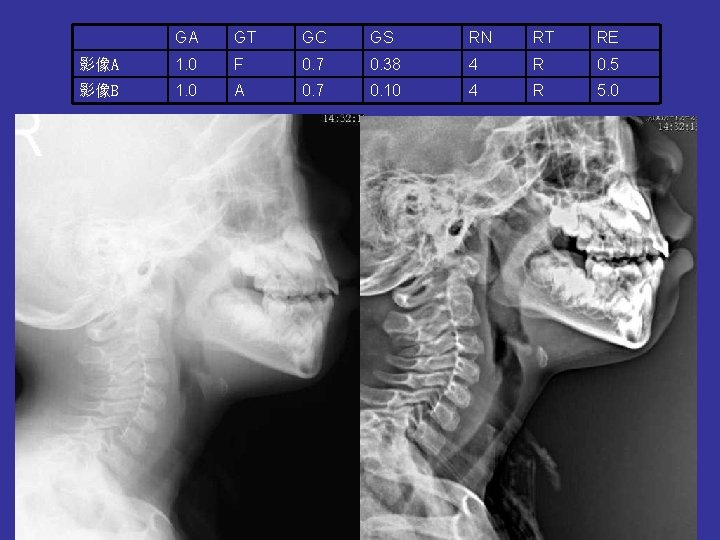

GA GT GC GS RN RT RE 影像A 1. 0 F 0. 7 0. 38 4 R 0. 5 影像B 1. 0 A 0. 7 0. 10 4 R 5. 0